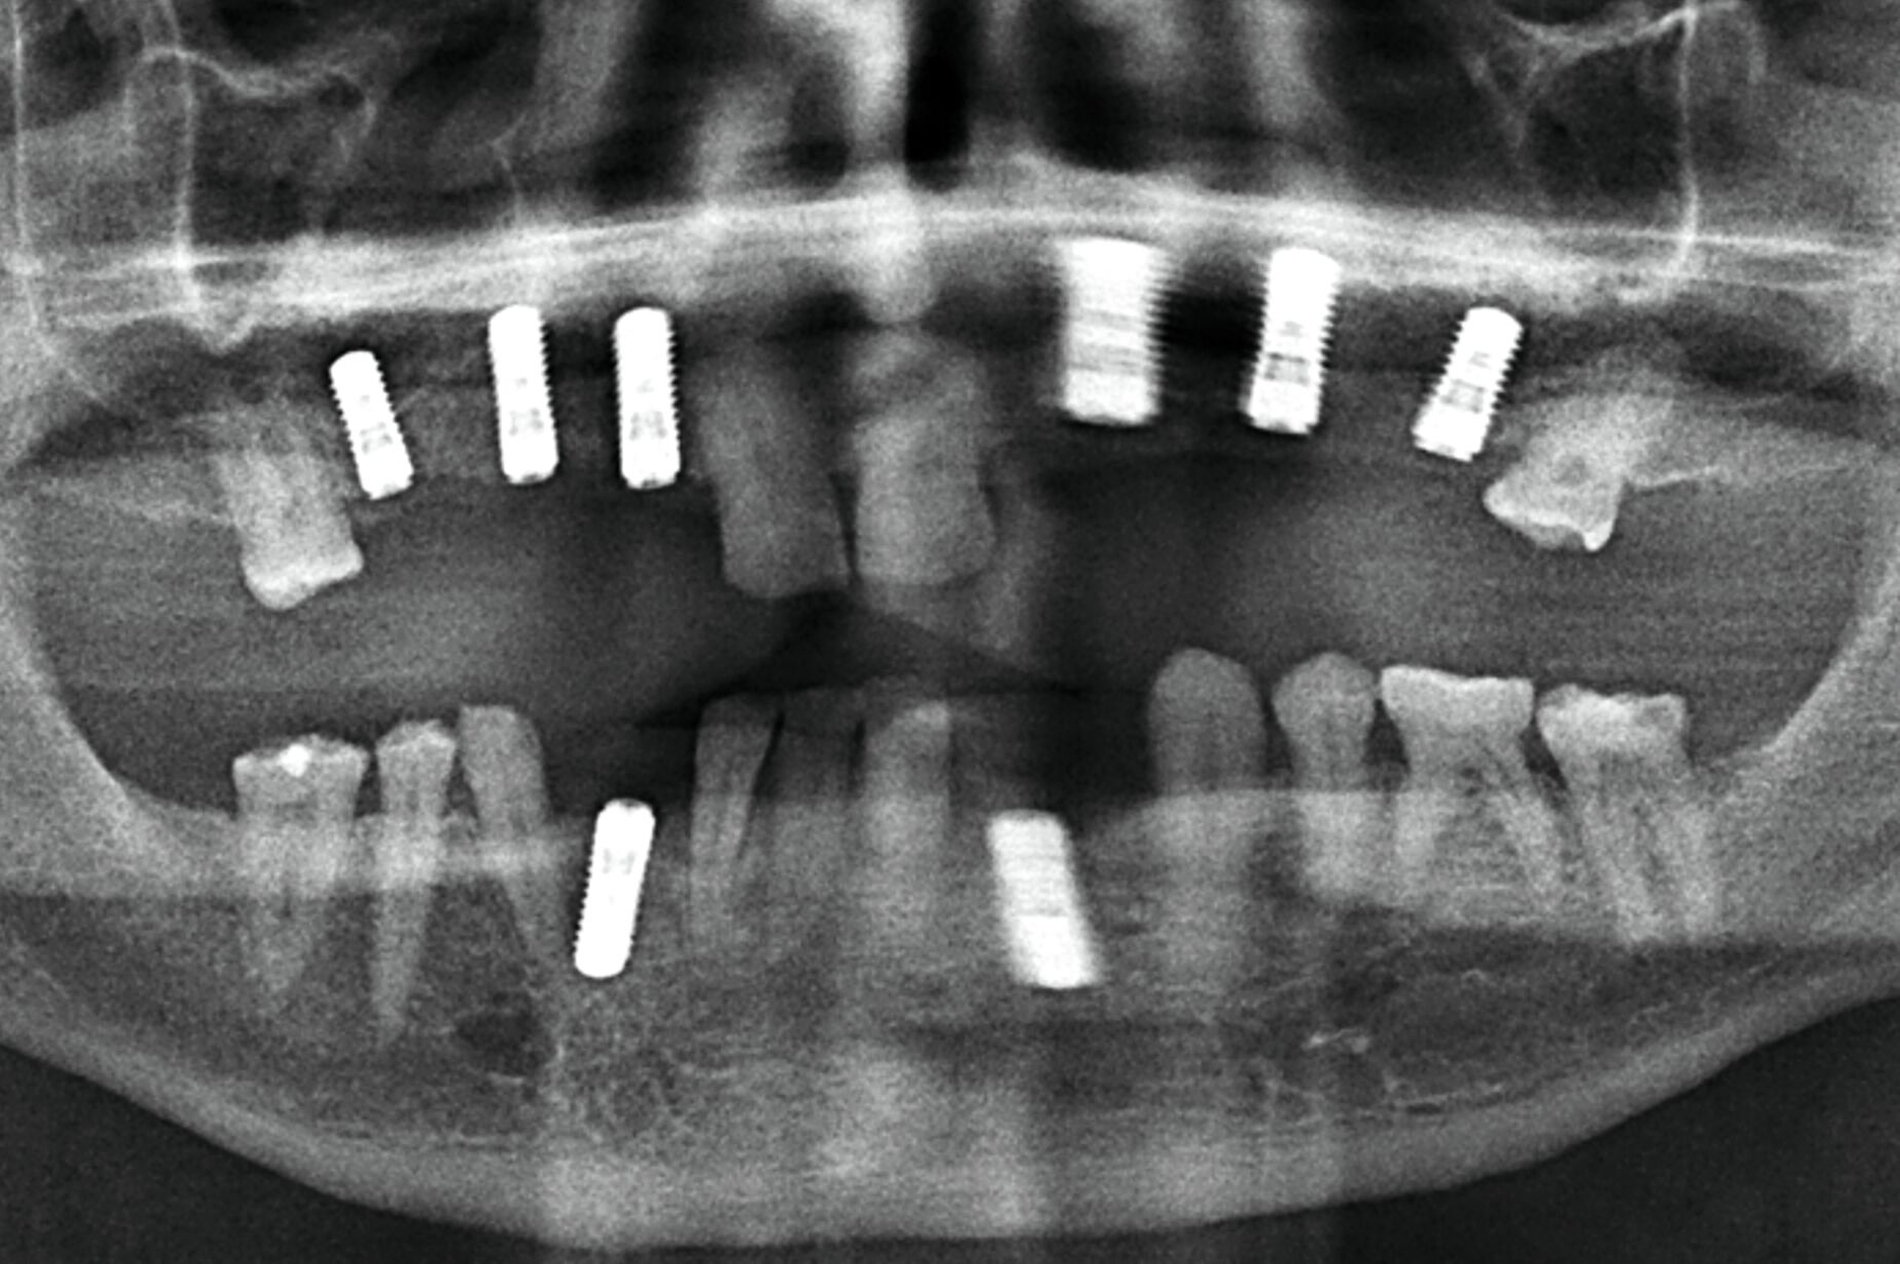

Zur Implantationsplanung wurden nach Abschluss der Vorbehandlungen und Prophylaxemaßnahmen zunächst eine digitale Volumentomografie (DVT) sowie aktuelle Situationsmodelle von Ober- und Unterkiefer zur Beurteilung der ossären Ausgangssituation erstellt. Es folgte die digitale Planung der Implantationen an den Regionen 12, 13, 13, 22, 23, 25, 33 und 43 (CoDiagnostiX Dental Wings, Straumann, Basel, Schweiz) sowie die Übertragung der dreidimensional geplanten Implantationen in gedruckte Bohrschablonen und die Festlegung von Art und Zeitpunkt erforderlicher Augmentationen (Abbildung 5).

Unter intravenöser Sedierung wurden Implantate im Ober- und Unterkiefer inseriert, kombiniert mit Sinusbodenelevation und vestibulären Augmentationen. Aufgrund unzureichender Knochenverhältnisse erfolgte an Regio 33 eine zweizeitige augmentative Maßnahme mit Schirmschrauben und Membran (Abbildung 6), gefolgt von der sekundären Implantation nach vier Monaten (Abbildung 7).